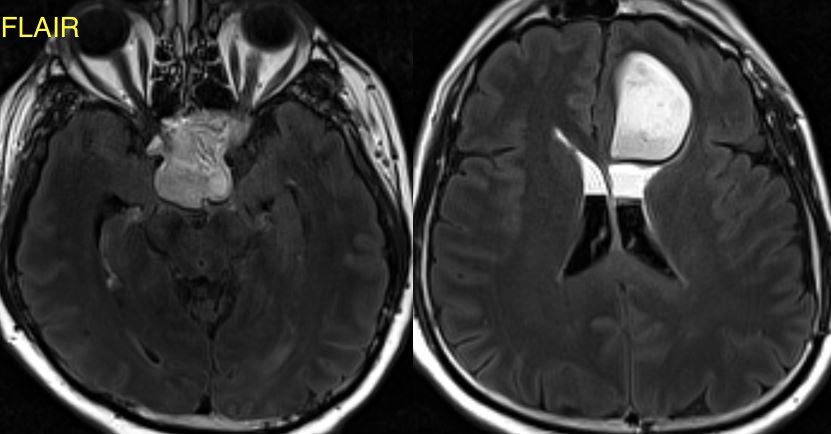

What is the most likely diagnosis in this 30 y/o patient with history of seizures presenting with severe headache?

More images in ๐Ÿงต

Additional images ๐Ÿ‘‡